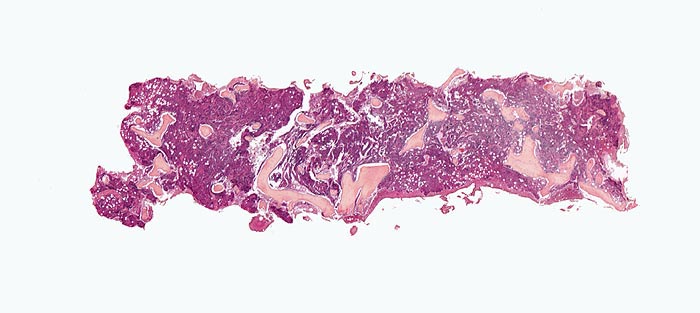

Knochenmark, Beckenkamm

- Osteosklerose: verplumpte und breite Knochenbälkchen.

- Kollagenfibrose.

- Dilatierte Sinusoide mit intrasinusoidaler Blutbildung.